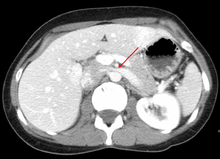

The nutcracker syndrome (NCS) — is a manifest variant of nutcracker phenomenon, renal vein entrapment syndrome, or mesoaortic compression of the left renal vein. It results most commonly from the compression of the left renal vein between the abdominal aorta (AA) and superior mesenteric artery (SMA), although other variants exist.[1][2] The name derives from the fact that, in the sagittal plane and/or transverse plane, the SMA and AA (with some imagination) appear to be a nutcracker crushing a nut (the renal vein). There is a wide spectrum of clinical presentations and diagnostic criteria are not well defined, which frequently results in delayed or incorrect diagnosis.[1] This condition is not to be confused with superior mesenteric artery syndrome, which is the compression of the third portion of the duodenum by the SMA and the AA.